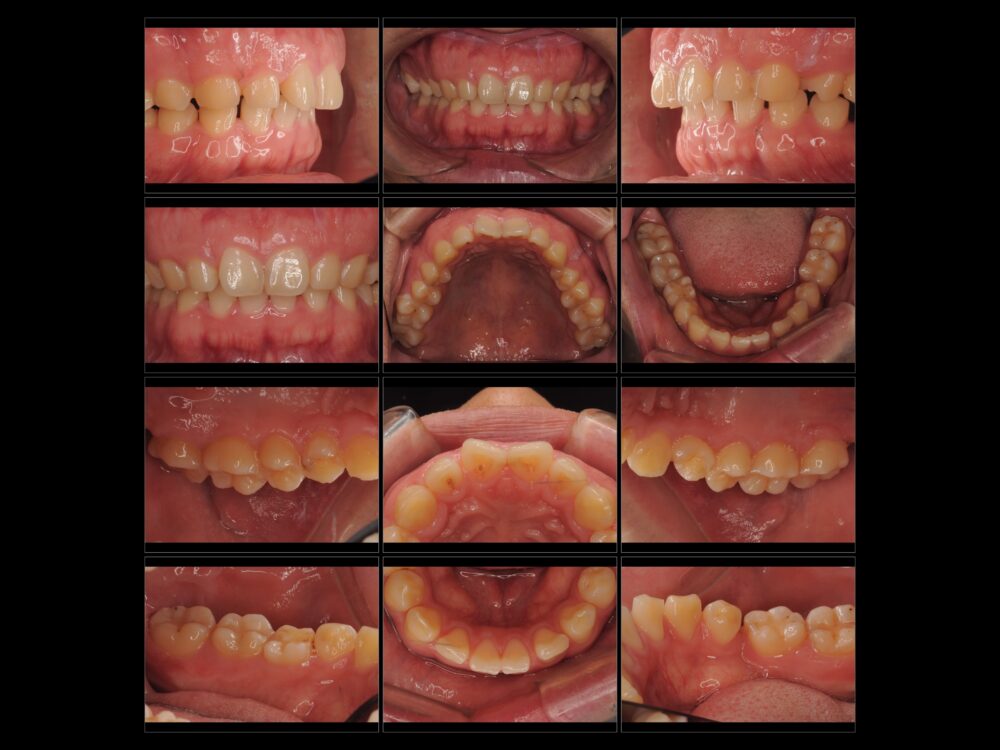

家族から「歯ぎしり」がひどいと指摘されたことが心配でお越しになりました。自分では10代後半に左下の奥歯(乳歯)が抜けてしまい、そのままにしていることで咬み合わせが悪くなったことが「歯ぎしり」の原因ではないか…と思っているとのことでした。

両側とも下の5番目の永久歯が生まれつきありません(先天的欠如歯)。

本人は乳歯しかないところがあることは知っていたようで、今回と同様の相談を1年前に他の歯科医院でもしたところ、矯正治療とインプラント治療が必要と言われたものの、治療には至らなかったそうです。

初診より約2ヵ月後、右下の乳歯の抜歯を行い、アライナー治療を開始しました。